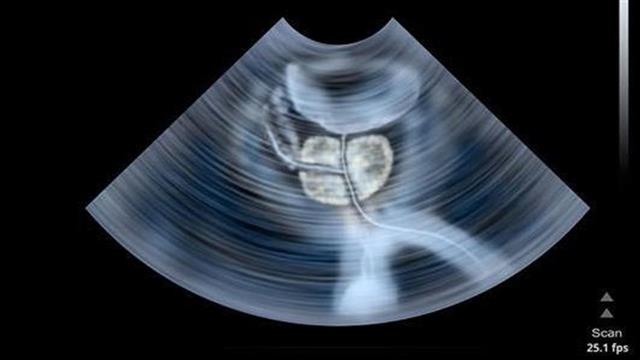

Βασική εξέταση είναι η δακτυλική εξέταση του προστάτη από το ορθό. Πληρέστερη εξέταση είναι το Υπερηχογράφημα Κύστεως και Προστάτη, που δίνει πολύ καλή εικόνα του εσωτερικού της κύστης και του προστάτη.